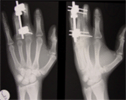

Digit lengthening in a 23 years old industrial worker

Traumatic Amputation of middle three fingers left hand at level of middle phalanx with terminilisation done

Lengthening proximal phalanx of middlefinger done using unilteral fixator at stages

2nd surgery to lengthen index and ring fingers